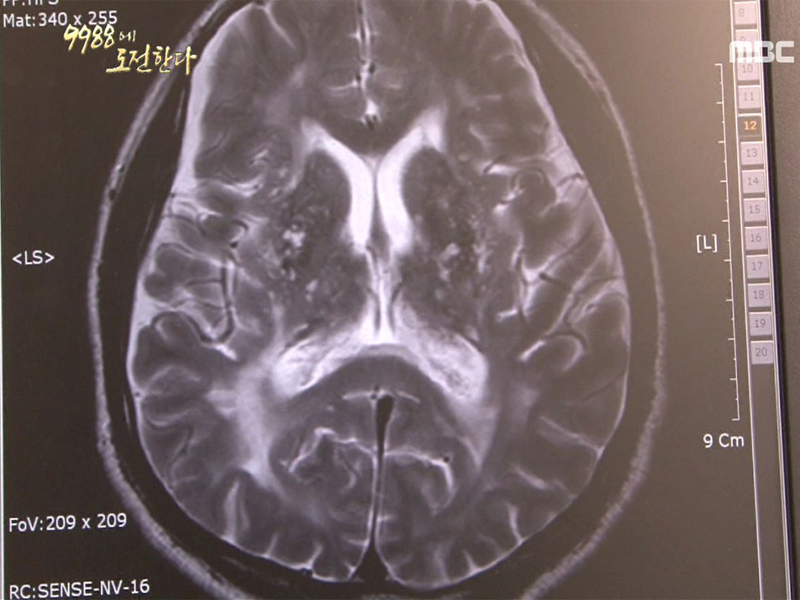

건강프로젝트 9988에 도전한다 “침묵의 질병, 고혈압“